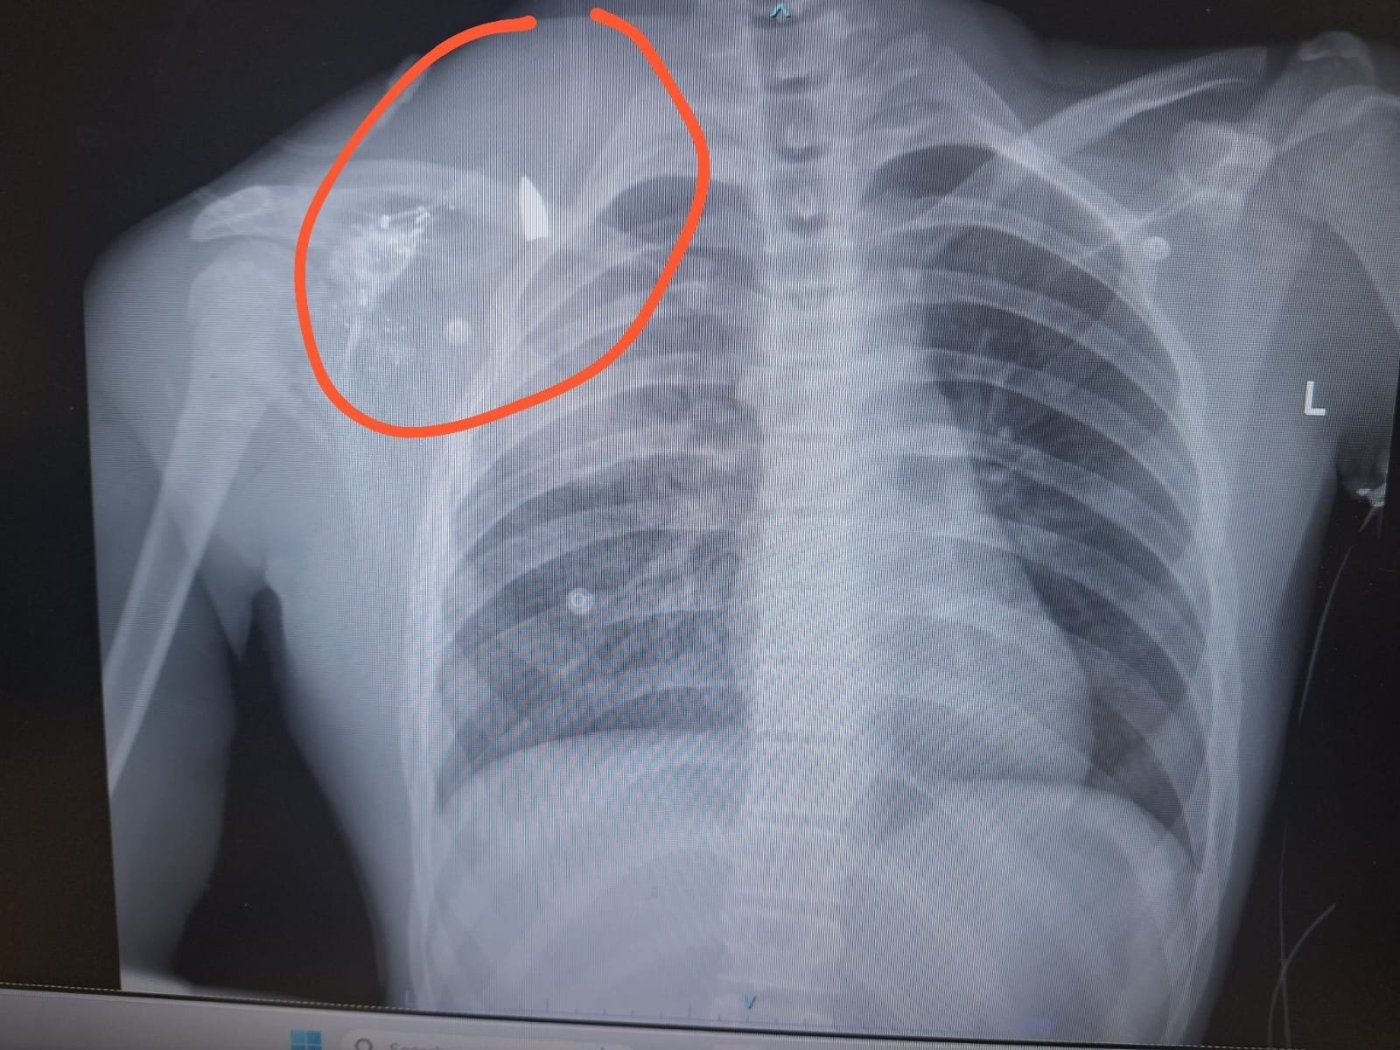

בתוך כך, בארגון "חוננו" טוענים כי נער בן 14, אסיף הלל בן אפרת, נפגע במהלך האירועים מירי חי שביצעו חיילים. לדברי הארגון, "צילום הרנטגן מוכיח - הקליע נכנס לזרועו ונעצר בגבו". לפי הדיווחים, הנער סובל מריסוק עצמות בכתף, פגיעת הדף בריאות ורסיסים נוספים.הוא הועבר מבית החולים הדסה הר הצופים למחלקה לטיפול נמרץ בהדסה עין כרם, וצפוי להיכנס מחר לניתוח.